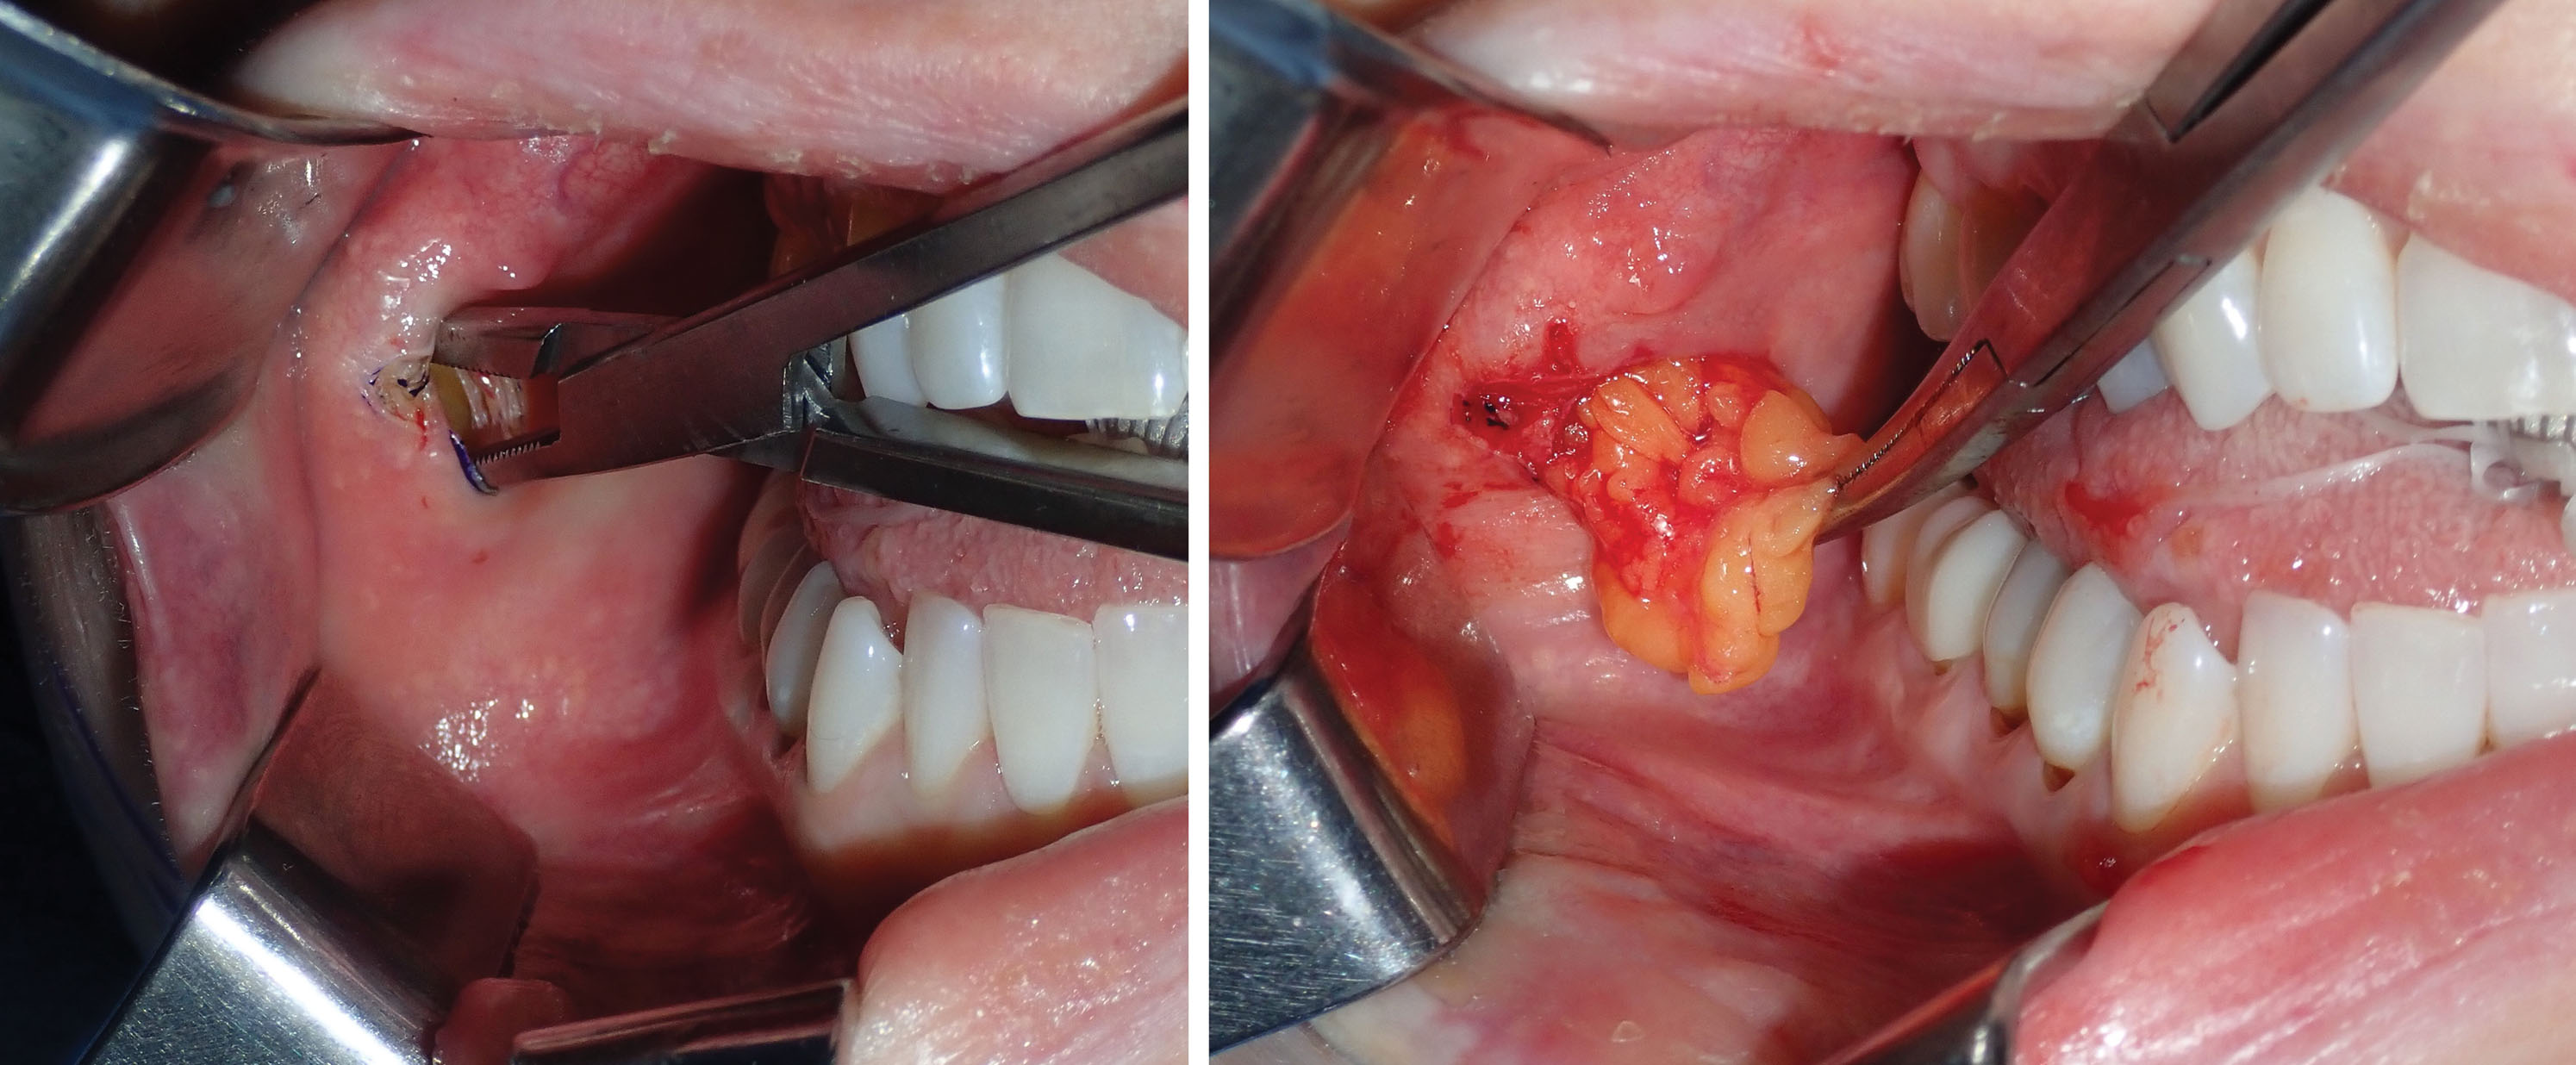

Once the available fat is delivered into the oral cavity, it is reduced with bipolar forceps or an electrosurgery tip at the base for coagulation ( Fig. 15.21 ). It is important to use a coagulative modality as vessels penetrate the fat pad in the same manner as blepharoplasty.

The end point of buccal fat reduction is gauged in a similar manner to blepharoplasty. The excess fat that readily presents itself with minor traction and superficial exploration is removed. Additional contributions to the end point are the lack of additional fat delivered into the mouth and visible depressions at the site of the BFP ( Fig. 15.22 ). Performing BFR is very similar to blepharoplasty in that overresection can produce a skeletonized appearance. Facial fat is a friend and not an enemy, and reduction should be judicious. Generally removing all of the easily available fat that herniates into the oral cavity with suction or moderate traction is sufficient for a noticeable clinical result.

Before transection, a photo is taken of the BFPs when delivered into the mouth. A photo is also taken of the excised specimen ( Figs. 15.23 and 15.24 ). This is done for medical records and also because every single patient is interested in how much fat was removed.